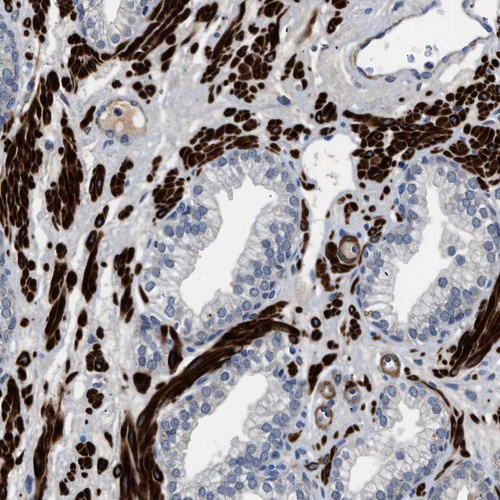

Immunohistochemical staining of human cerebral cortex shows strong nuclear positivity in neurons.